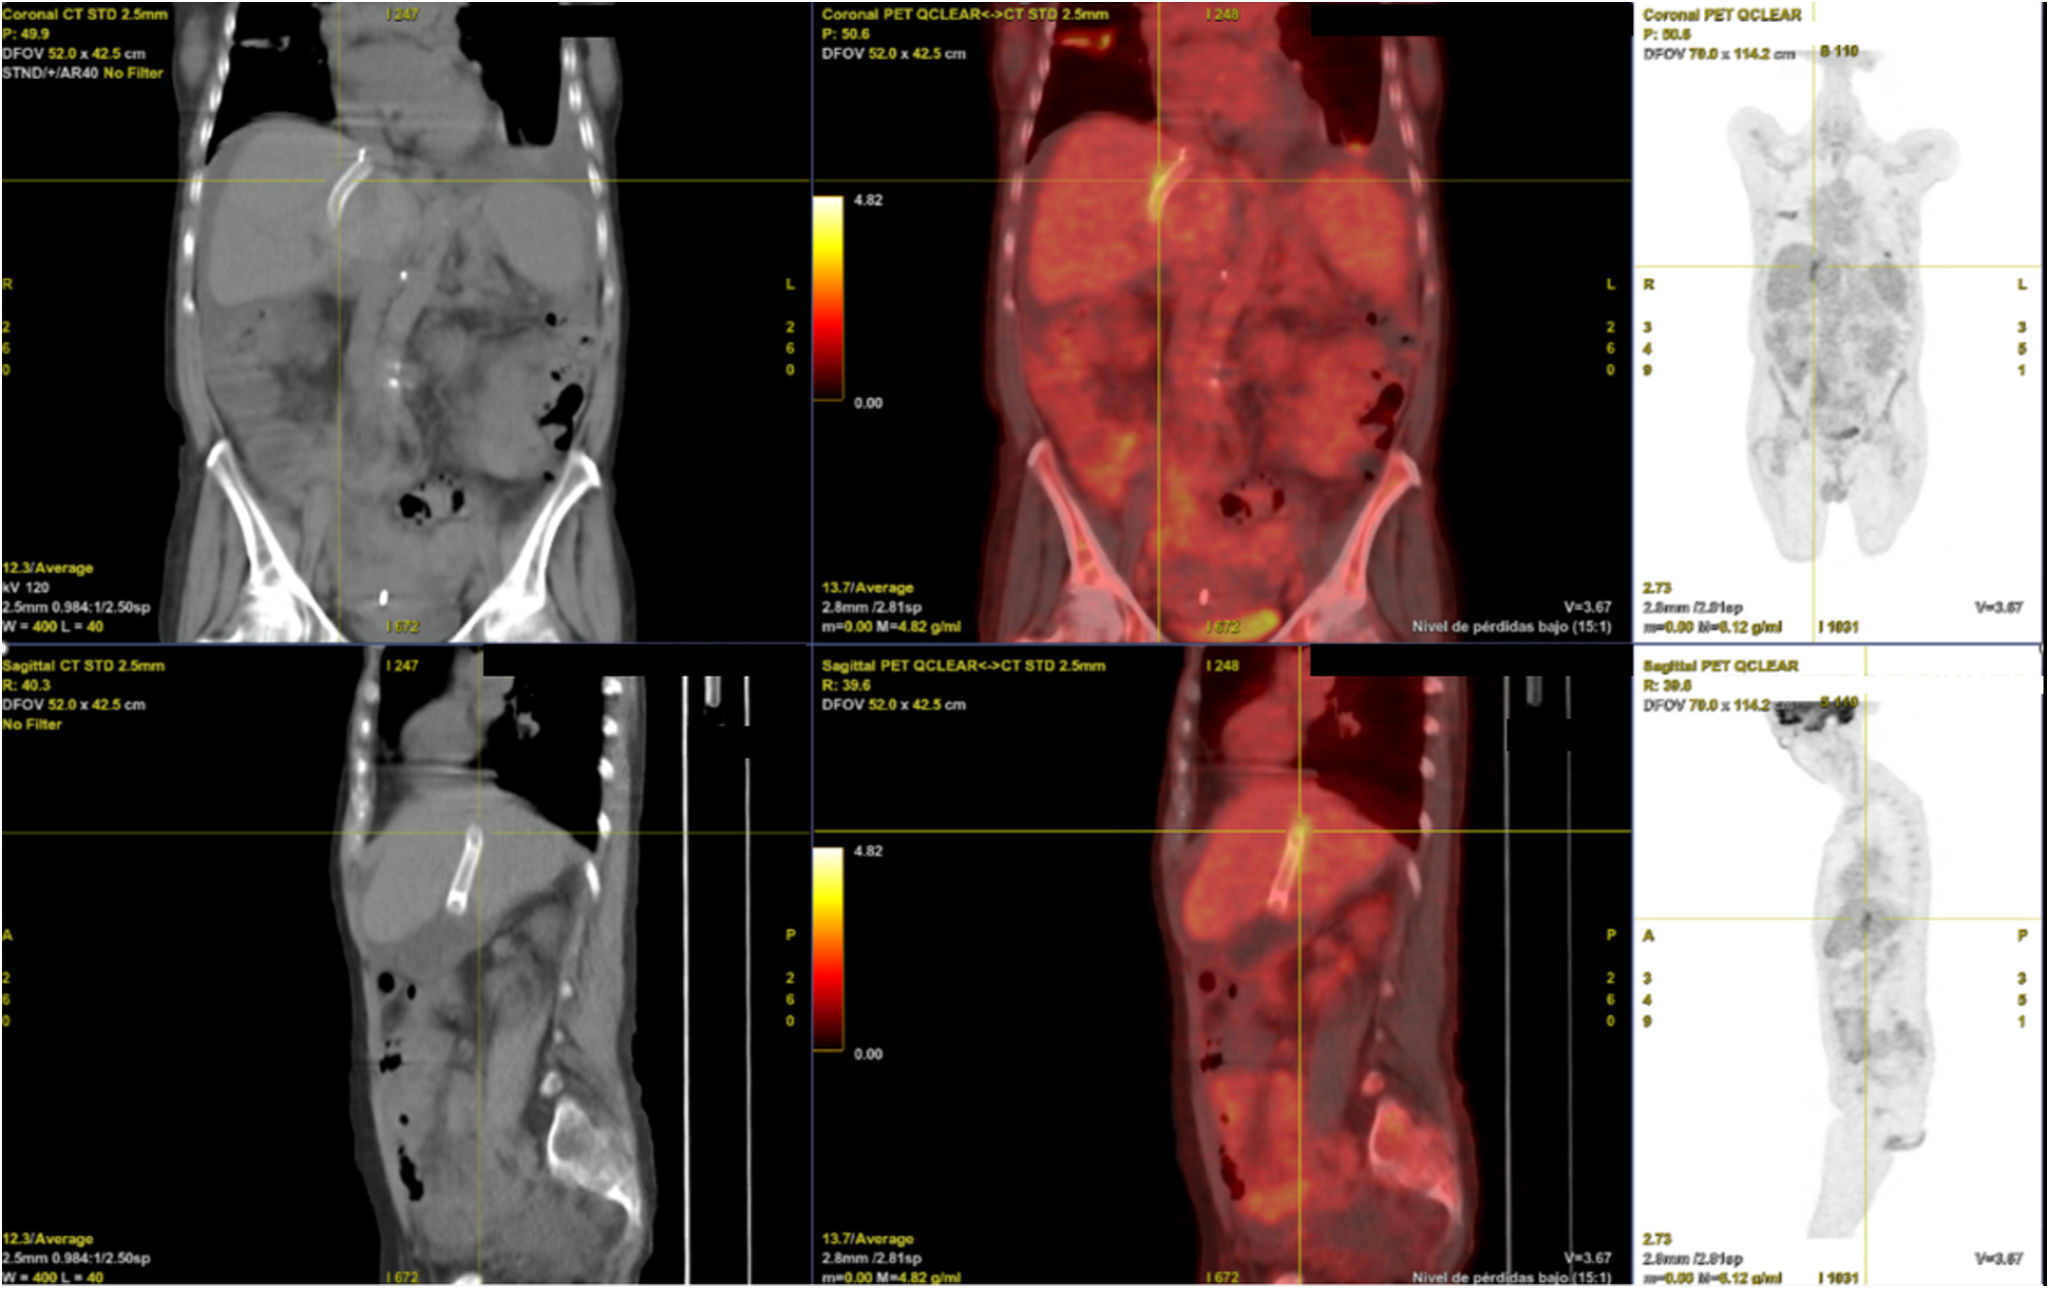

Más allá del TIPS permeable: El papel del PET/TC en la endoTIPSitis

Beyond a permeable TIPS: The diagnostic role of PET/CT in endoTIPSitis